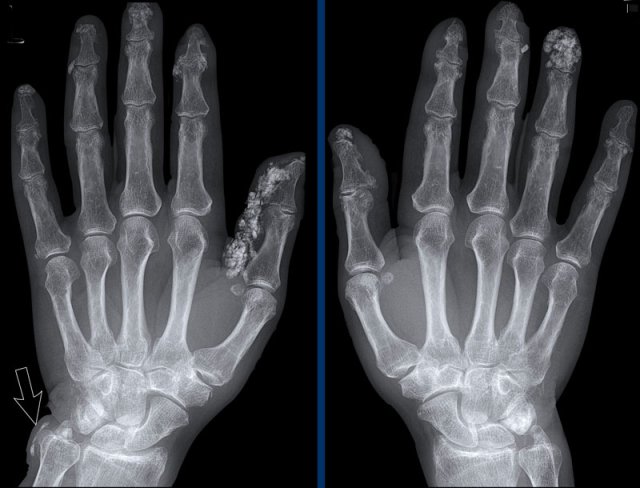

Soft tissue calcifications

Extensive soft tissue calcifications in the distal phalanges in a patient with scleroderma.

Notice the calcifications next to the distal ulna (arrow).

There are no signs of cartilage damage.

The pathophysiology of the calcium deposits is not well understood.

It occurs in tissues that are under chronic stress, such as local trauma or damage associated with an underlying inflammatory process.

It is usually more abundant in the dominant hand.

When these findings are present, the diagnosis is usually straight forward.

Subtle, but coarse soft tissue calcifications at the most distal part of the finger in a patient with scleroderma.

No acro-osteolysis or other signs are seen.

Acro-osteolysis in Scleroderma

Severe acro-osteolysis of the finger tips of dig 1-3 in a patient with scleroderma (arrows). Notice the lysis of the soft tissues distally.

Acro-osteolysis is a radiographic finding which refers to bone destruction of the distal phalanges and occurs in 6–65% of patients with scleroderma.

Vascular alterations and reduced capillary density impair tissue oxygenation and the resulting hypoxia may contribute to osteoclast activation.

There is a wide variety of diseases that can cause acro-osteolysis including psoriatic arthritis, infection, raynaud disease and thermal trauma.